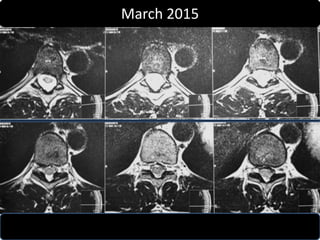

• Follow up MRI was done March 2015

• Complete absorption of fragmant.

March 2015

D10 – D11

D11